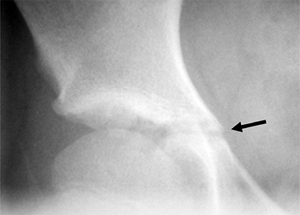

Figure 18.16 The triradiate cartilage of the acetabulum is seen here (arrow).

The closure of this growth cartilage signifies completion of the most rapid phase of adolescent growth. However, at least 2 years of growth may be remaining following closure of the triradiate cartilage.  |